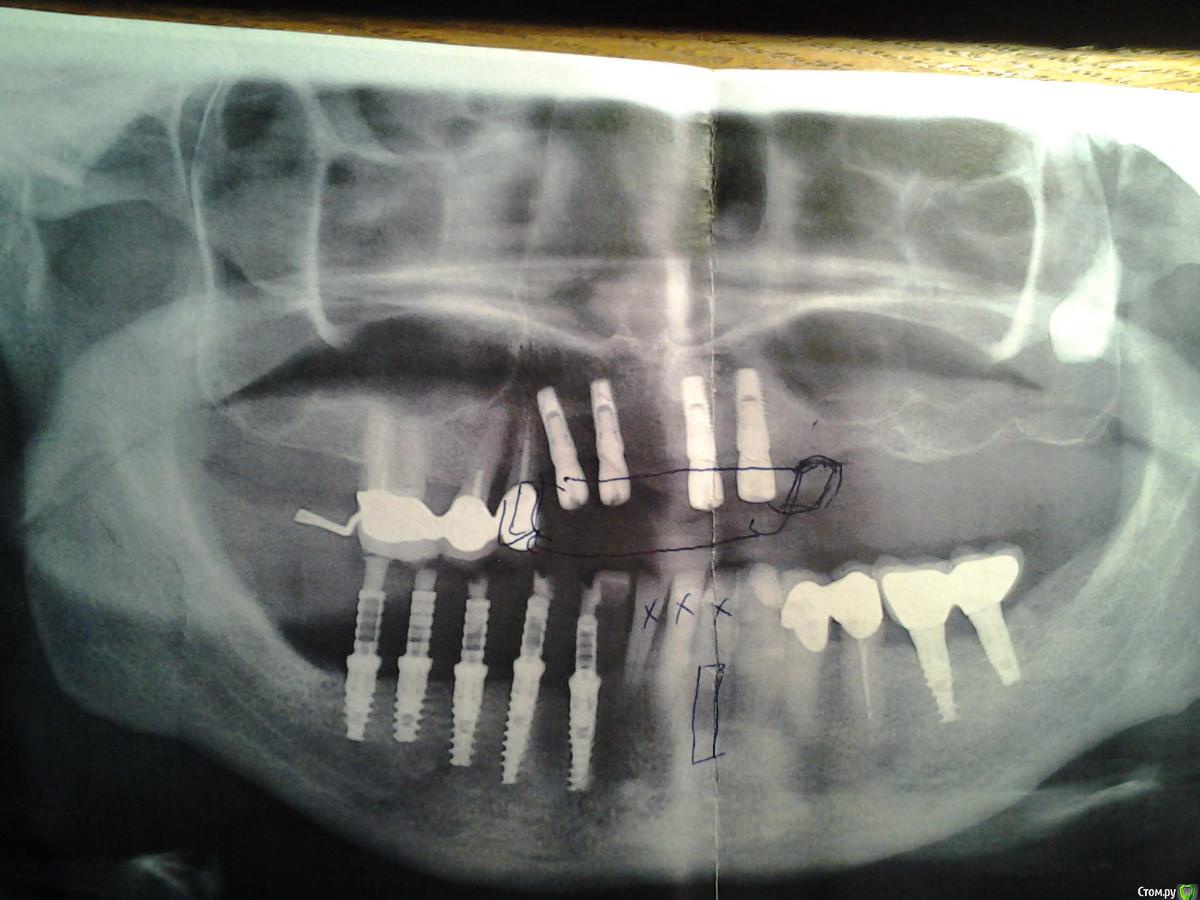

fannina Опубликовано 1 декабря, 2015 Поделиться Опубликовано 1 декабря, 2015 Доброй ночи, уважаемые стоматологи. Два года занимаюсь имплантацией. Истратила ужасное количество денег. Нахожусь в полной растерянности. Не знаю: что делать?, где делать? На верхней челюсти на данный момент стоят Implantium 4 штуки, 3 своих зуба удалены. Планировалось сделать съемный на балке. Очень напрягает, что импланты как-то развернуты (видно на фото), два практически совпадают по расположению с краем зубов (бывших), не будет ли протез на балке слишком широким и не будет ли он очень выпирать в сторону губы. Как будут вести себя импланты, которые реально не находятся вдоль одной дуги, не будут ли расшатываться? На нижней челюсти с одной стороны стоят 2 импланта (забыла какие) под постоянными коронками. С другой 5 имплантов Alfa-bio. На них уже больше года стоит временный мост. С нижней челюстью совсем неясно. Как планировалось изначально с врачом протезистом : на 4 зуба поставить постоянный мост из 5 коронок, а на один (передний) поставить опять временную, чтобы в дальнейшем удалить передние 3 зуба, поставить еще один имплант и на 2 импланта поставить передние 4 зуба, на оставшиеся 3 своих зуба надеть мост из 3 коронок. Врач имплантолог говорит, что так не получится, потому что передний имплант предназначен почти на 2 зуба, если он будет стоять отдельно, то моментально выпадет. Ставить сейчас еще один имплант очень проблематично, не говоря о том, что плохо с деньгами, совсем плохо со временем, ждать пока приживется имплант нет мочи. С верхней челюсти постоянно слетает протез, в этом месяце сломался второй раз. Изначально планировалось делать верхнюю и нижнюю челюсть вместе, чтобы все выровнять. Изначально я планировала удалять свои передние зубы (следующим этапом). Косная ткань там в значительной степени отошла, они совсем не нравятся мне внешне, но в них нет даже намека на шатание, то что они явно сдвинулись, произошло от того, что на том месте, где сейчас стоят два импланта с ранней юности ,25-30 лет ничего не было. Подскажите, возможен ли вариант: поставить 6 коронок на 5 имплантов, и мост на 6 своих зубов. Это продлит, или укоротит существование своих зубов, которые планируется удалить, не расшатает ли те зубы, которые удалять не планируется. Этот вариант устроил бы даже как временный. Еще хотела вас спросить, можно ли повторно использовать абатменты, которые стоят у меня в 5 имплантах.Оцените, пожалуйста, ситуацию. Очень-очень надеюсь на ваши советы и помощь.Прикрепленные изображения Ссылка на комментарий

Bier Опубликовано 3 декабря, 2015 Поделиться Опубликовано 3 декабря, 2015 Спасибо за ответ. Попробую еще раз сформулировать точнее. По верху: 1.Будет ли протез на балке слишком выпирать в сторону губы, т.к. два из четырех верхних импланта расположены по самому краю моих бывших зубов(у губы) и еще развернуты в сторону губы. 2. Не будет ли балка на таких имплантах непрочной конструкцией, т.к. два импланта стоят чуть дальше в направлении от губы и развернуты в сторону неба, а два чуть ближе и развернуты в сторону губы По низу. Согласна с вами, что эти зубы все уйдут. На данном этапе возможен ли такой вариант:1. На импланты, которые установлены поставить постоянный мост. 2.На оставшиеся шесть своих зубов поставить мост или не делать ничего. В каком случае временный период продлится дольше?К сожалению все удалить, поставить импланты и сделать один красивый мост нет возможности, это связано с целым рядом причин, хотя понимаю: это все впереди. 3. Я не знаю временные у меня абатменты стоят или нет, мост временный, если судить по цене абатментов, то постоянные. 4. Если воспользоваться вашим советом, то следует сделать временный мост сразу почти на весь низ, или есть возможность каким-то образом прикрепить его к имеющемуся. Имеющийся стоит уже очень давно: больше года. Возможно это чисто субъективное восприятие, что у меня все сложно. Ставила я импланты в клинике (совместное предприятие), цены выше среднего. Сейчас ситуация изменилась. Попробовала обратиться в другие клиники по рекомендациям знакомых. В одном месте очень пожалела, что не пришла к ним сразу. Но, к сожалению, столкнулась с тем, что с Имплантиумом, который у меня сверху, клиники, в которые я ходила, не работают (ходила в три), с альфа-био - работают все три. Посоветуйте, пожалуйста, кто бы смог мне помочь и как мне разумно поступить.1. протез на балке в любом случае несколько выдается ветибулярно, с положением имплантатов это не сильно связано. В большинстве случаев губе нужна поддержка в виде базиса протеза т.е. может это и не плохо. Но тут мало диагностической информации для полноценного ответа. Нужны фото в профиль, ТРГ, примерки на воске.2. нет, не будут.По низу: это временные абатменты (видно по снимку)можно пока не трогать нижние зубы и оставить все как есть. Не вижу при этом смысла менять вообще что либо. Ходите с временными коронками.Прикрепить мост к имеющемуся - очень сомнительно, скорее всего в этом месте сломается. Ссылка на комментарий